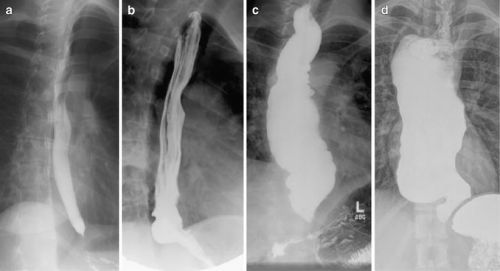

Помимо такой классификации, заболевание можно разделить еще на два вида, при этом необходимо отталкиваться от рентгенологических признаков, которые могут проявляться:

- Первый тип можно встретить в 60% всех случаев заболевания. При этом можно обнаружить сужение пищевода или расширение пищевода. В зависимости от этого, возможно изменение формы пищевода на более цилиндрическую.

- Во втором случае, определенный отдел пищевода уже значительно сужен, при этом его мышечная оболочка является атрофичной.

У больных с кардиоспазмом при рентгенологическом исследовании выявляют усиление моторики пищевода с выраженными сегментарными сокращениями, при ахалазии кардии — снижение моторной активности пищевода (отсутствие первичной перистальтики в дистальных 2/3 пищевода).

Рентгенологическими признаками кардиоспазма являются расширение пищевода в той или иной степени с наличием «узкого сегмента» в терминальном его отделе. Стенки пищевода, в том числе и в суженной части, сохраняют эластичность. В расширенном пищеводе натощак определяется значительное количество жидкости.